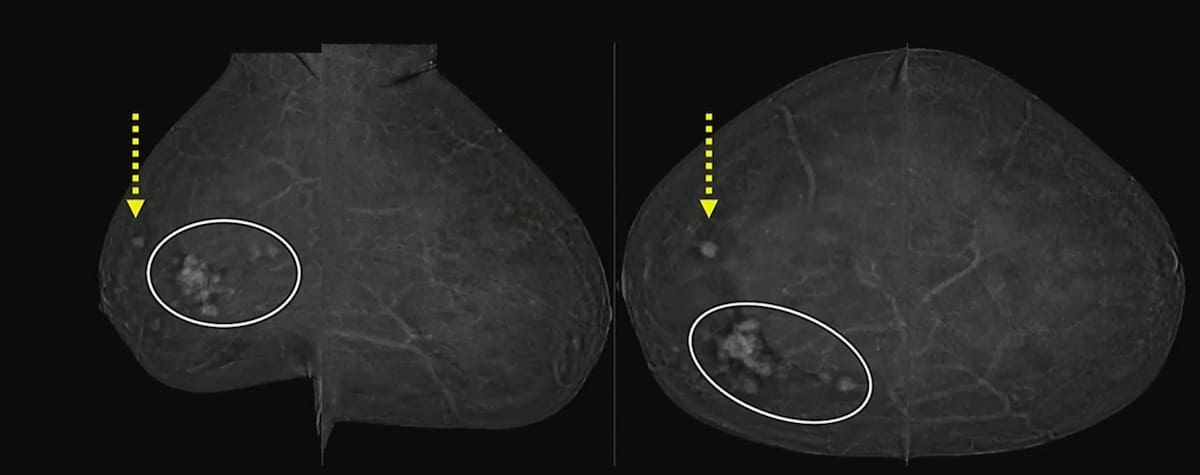

Additional carcinoma in the ipsilateral breast was detected on preoperative MRI exams in 24 out of 102 women prior to lumpectomy and mastectomy procedures, according to new study findings presented at the 2024 American Society of Clinical Oncology (ASCO) Annual Meeting in Chicago.

In a recent lecture at the 2024 ARRS Annual Meeting, Jordana Phillips, MD, discussed the role of contrast-enhanced mammography in staging breast cancer, evaluating response to neoadjuvant chemotherapy and recalls from screening.